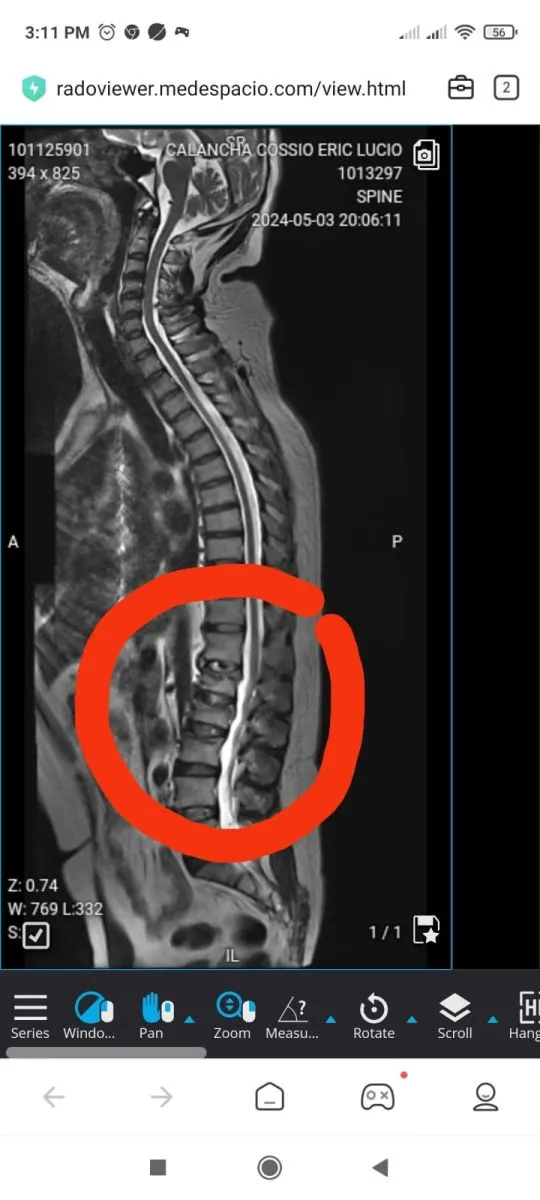

Calancha tiene aplastamiento de las tres primeras vértebras lumbares, sobre todo de la primera y segunda, "donde se puede observar disminución de la altura del cuerpo vertebral". Esta situación provoca fuertes dolores al actor, pese a estar medicado y puede producir una inestabilidad en la espalda, según la artista Graciela Tamayo.

Una de las radriogafías de Calancha.    FOTO: Eric Calancha

En estos casos lo más recomendable es realizar una vertebroplastia, que consiste en aplicar una especie de cemento, en las vértebras afectadas. "Tras el procedimiento Eric ya no sentirá dolor y se estabilizará su columna. Algo muy importante ya que, muy aparte, se aprecian también signos de artrosis", agregó Tamayo.